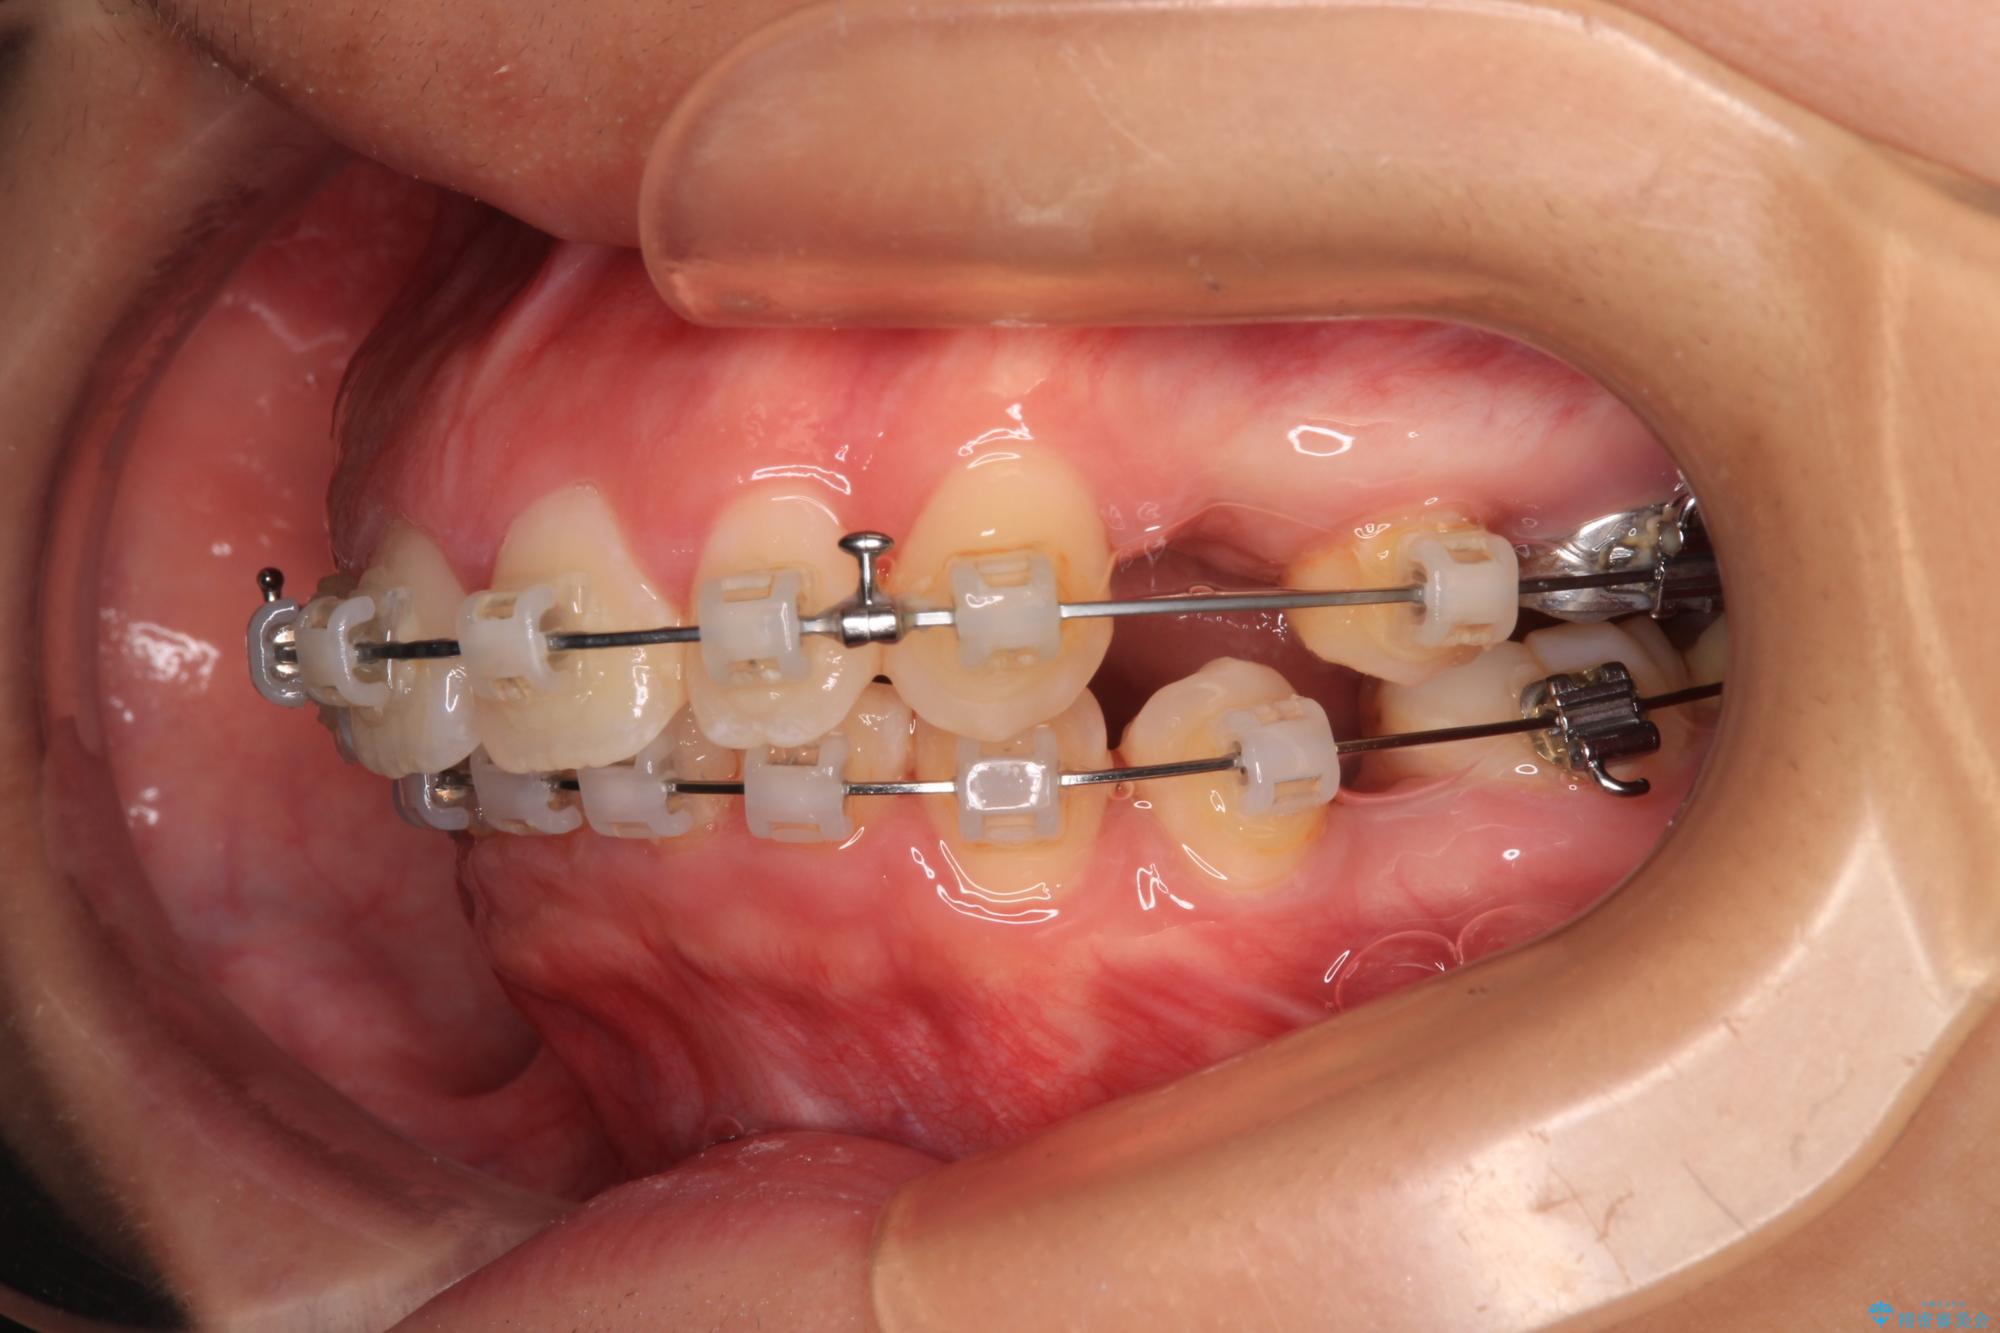

- 矯正装置

- クリアブラケット

また、上顎歯列が下顎に対して前方位に位置していたため、補助装置を用いて上顎歯列を後方に移動させ、より積極的に口元を下げるようにしました。

上下正中位置を改善するため、左下はイレギュラーに第二小臼歯を抜歯しました。そのため治療期間の長期化が予想されましたが、2年半ほどで期待通りの歯列に仕上げることができました。